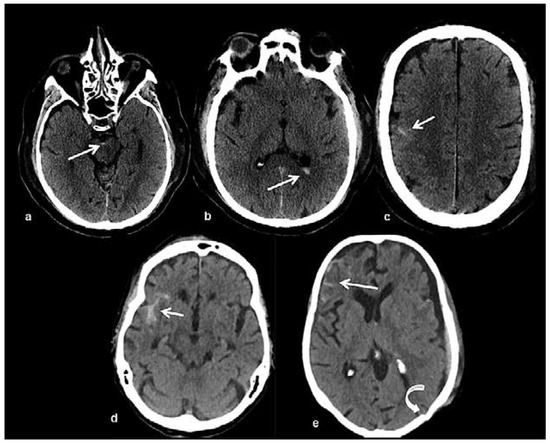

Head and brain trauma: general aspects and neuroimaging

by Johanna Maria Lieb, Christoph Stippich and Meritxell Garcia

In this article the general clinical aspects, imaging indications and different injury mechanisms of traumatic brain injury (TBI) are reviewed. In addition, the different imaging modalities and strategies are presented, including more specific imaging features of the various injuries. Computed tomography (CT) is [...] Read more.

In this article the general clinical aspects, imaging indications and different injury mechanisms of traumatic brain injury (TBI) are reviewed. In addition, the different imaging modalities and strategies are presented, including more specific imaging features of the various injuries. Computed tomography (CT) is the imaging modality of choice in the acute phase owing to its wide availability and short scanning time, as well as to its high sensitivity for the detection of fractures and acute bleeding. Although magnetic resonance imaging (MRI) is superior to CT in many other aspects, it plays no role in the acute phase. MRI, however, has been proven to be useful and complementary to CT in the subacute and chronic stages as well as in the case of inconclusive results on initial CT. Especially the use of standard sequences like fluid attenuated inversion recovery (FLAIR), diffusion and susceptibility weighted imaging (DWI and SWI) have been shown to increase the diagnostic potency in diffuse axonal injury, in mild brain trauma and also in more chronic stages of TBI. The use of more advanced MRI techniques such as diffusion tensor imaging (DTI), magnetic resonance spectroscopy (MRS), functional MRI (fMRI) and magnetic transfer imaging (MTI) can further complete the diagnostic evaluation and give insights into different pathophysiological processes in TBI. Full article